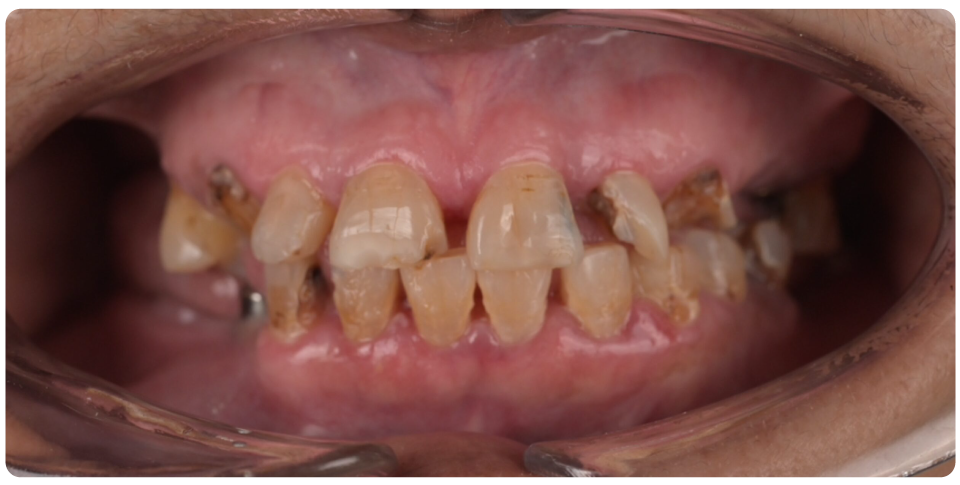

Complex Implant Rehabilitation

Complex dental implant rehabilitation is a highly effective solution for patients with extensive dental issues.

Such as severe bone loss, multiple missing teeth, cases involving tumor resection and reconstruction with vasculised bone grafts, gun shot injuries, with cleft lip and palate, jaw necrosis, post cancer oral rehabilitation.

Treatment plan includes Detailed clinical and radiographic evaluation of the patient’s general and oral health, including gum condition, remaining teeth, and bone structure with 3D scans, X-rays, and CT scans.